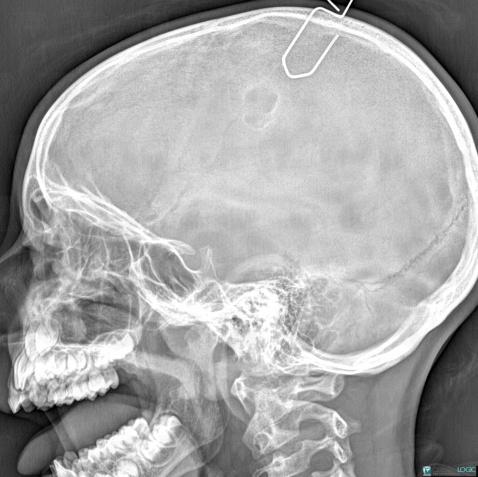

- Diagnostic Kyste dermoïde, Localisation(s) Voute du crâne, comportant les gammes Lésion ostéolytique du crâne